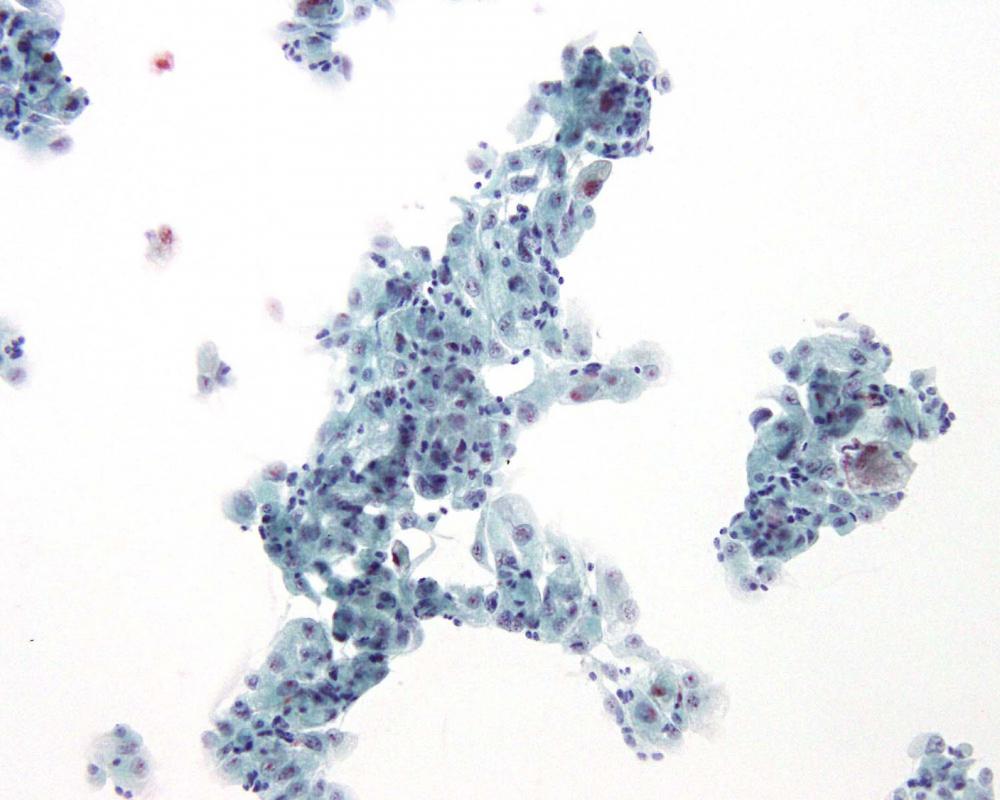

種別:泌尿器

| 採取部位 | 尿 | 採取方法 | 自然尿 |

臨床所見

既 往 歴:高血圧、高尿酸血症、PSA高値(9.17ng/ml)

現 病 歴:夜間頻尿にて受診。MRI検査にて、膀胱内腔へ突出する腫瘍が見られた。前立腺癌の尿道浸潤もしくは膀胱腫瘍が疑われた。

| 正解 | 4.膀胱原発腺癌 |